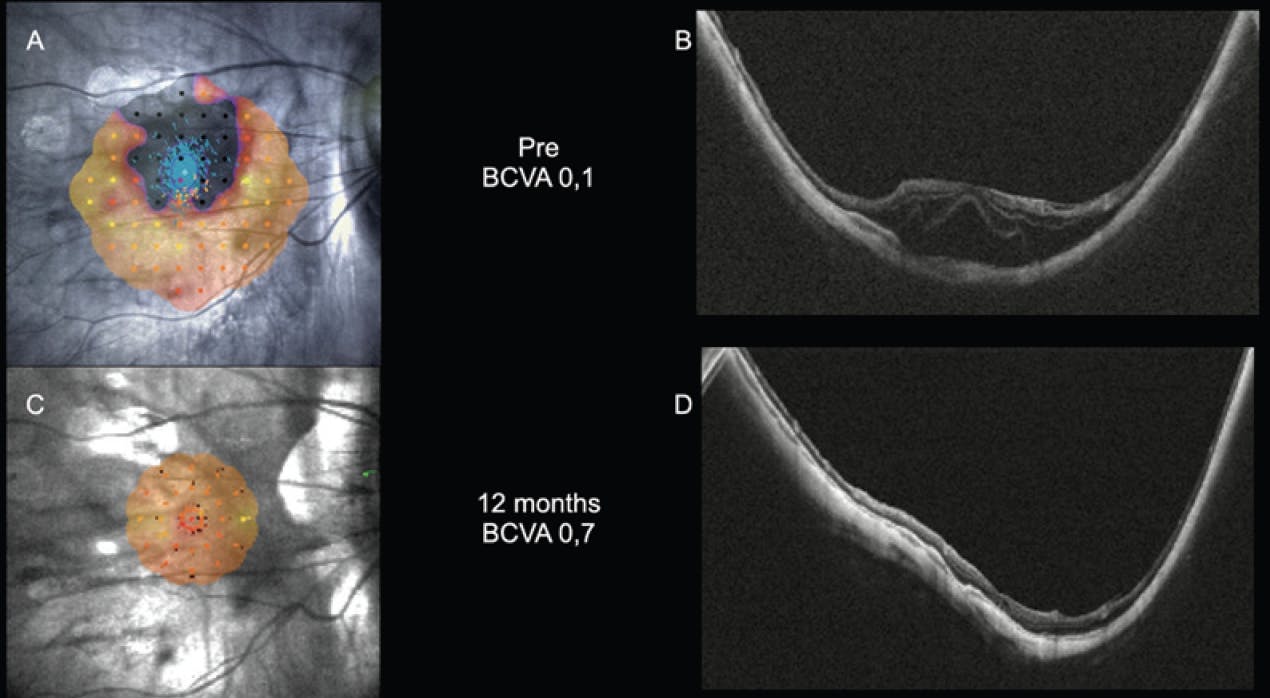

Case No. 2: A 47-year-old male presented with MTM Stage 3A (Figure 2A). His BCVA was 0.05 with a spherical equivalent of -22.0 D and an axial length of 31.7 mm. Microperimetry showed a large scotoma (Figure 2B). The patient underwent a 30-minute MB-only procedure. One month after surgery, the retina was attached (Figure 2C) and remained attached until the 12-month follow-up visit. His BCVA improved to 0.7 with a spherical equivalent of -19.0 D. Microperimetry showed the disappearance of the scotoma postoperatively (Figure 2D).

<p>Figure 2. MTM Stage 3A (A). Microperimetry showed a large scotoma (B). One month after surgery, the patient’s retina was attached (C), and microperimetry showed the disappearance of the scotoma (D).</p>

Figure 2. MTM Stage 3A (A). Microperimetry showed a large scotoma (B). One month after surgery, the patient’s retina was attached (C), and microperimetry showed the disappearance of the scotoma (D).